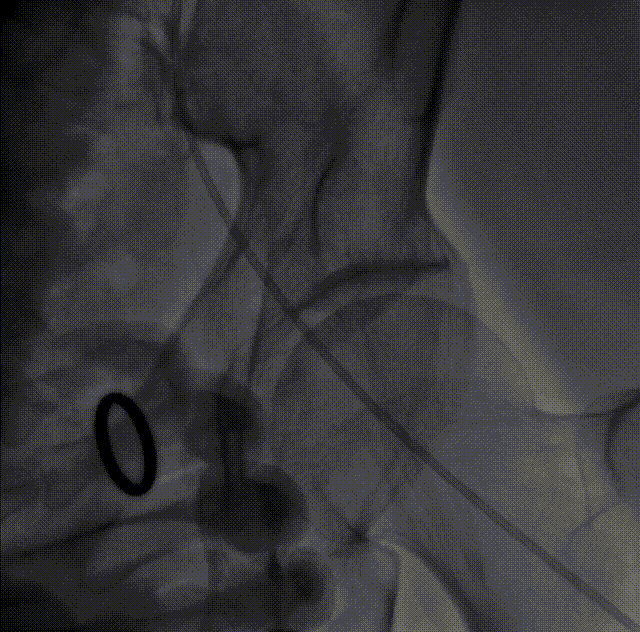

LM烟囱支架植入4.0*30mm

ECG术后即刻